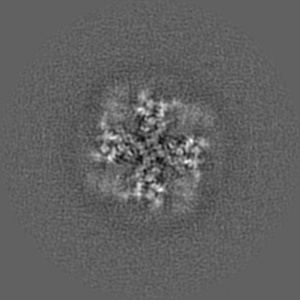

Cryo-EM structure of minimal TRPV1 with 2 bound RTX in opposite pockets

Sample: minimal TRPV1 in nanodisc

Fitted models: 7mze

Structural snapshots of TRPV1 reveal mechanism of polymodal functionality.

Zhang K , Julius D, Cheng Y

(2021) Cell , 184 , 5138